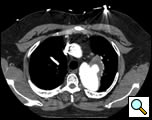

The patient is a 33 year old male with a history of juxtaductal coarctation who underwent a repair early in infancy. The patient had a recurrence of the coarctation and underwent a second open repair and left diaphragm plication at 2 years of age. He was lost to follow-up until recently when he presented to an emergency room with a several week history of hemoptysis and left back pain. The patient’s physical exam was remarkable only for a well-healed left thoracotomy incision. The patient was afebrile with equal blood pressures in all 4 extremities. The patient’s white count was normal. A CT scan of the chest demonstrated a saccular aneurysm of the proximal descending thoracic aorta measuring approximately 6cm in diameter (Figure 1). The patient was transferred to the Oregon Health and Sciences University for further management.

At our institution a dedicated CT angiogram of the chest was obtained to better define the morphology of the patient’s arch and aneurysm. This confirmed the finding of a saccular aneurysm just distal to the left subclavian artery takeoff. Because of the patient’s prior history of coarctation recurrence and repair, this was felt most likely to represent a pseudoaneurysm, possibly at the site of a patch repair. Aortic reconstructions of the CT angiogram showed no evidence for recurrence of the coarctation (Figure 2). There was, however, a size discrepancy in the diameter of the aorta above and below the aneurysm. The diameter of the aortic arch between the left carotid and left subclavian arteries was 13mm. The diameter of the descending thoracic aorta distal to the aneurysm was 23mm.